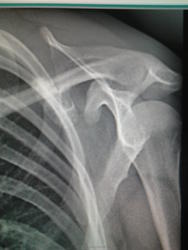

Девушка,1989 г.р.жалоб нет никаких,со слов в том году проходила флг(не у нас)-норма.Вызвала на рск,покрутила-тень смещается вместе с лопаткой,с ребрами не связана.Что это может быть слева на лопатке?остеохондрома?

Поддерживаю остеохондрому

+1.Но, для уточнения попытался  бы просмортреть ФЛО-архив, в плане динамики изменений  (  можно предположоить, что изменения имели место , но были пропущены, хуже если их правда не было...) Может помочь сбор жалоб и анамеза заболевания.  Показана КТ  органов грудной клетки.

Я бы изменения именовал остеомой. И без архива, без жалоб назначил бы... плановый рентген-контроль...